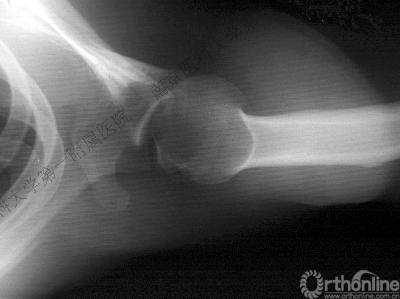

男性,27岁,车祸致右肩部肿痛、活动受限6小时。

术后肩关节X线片